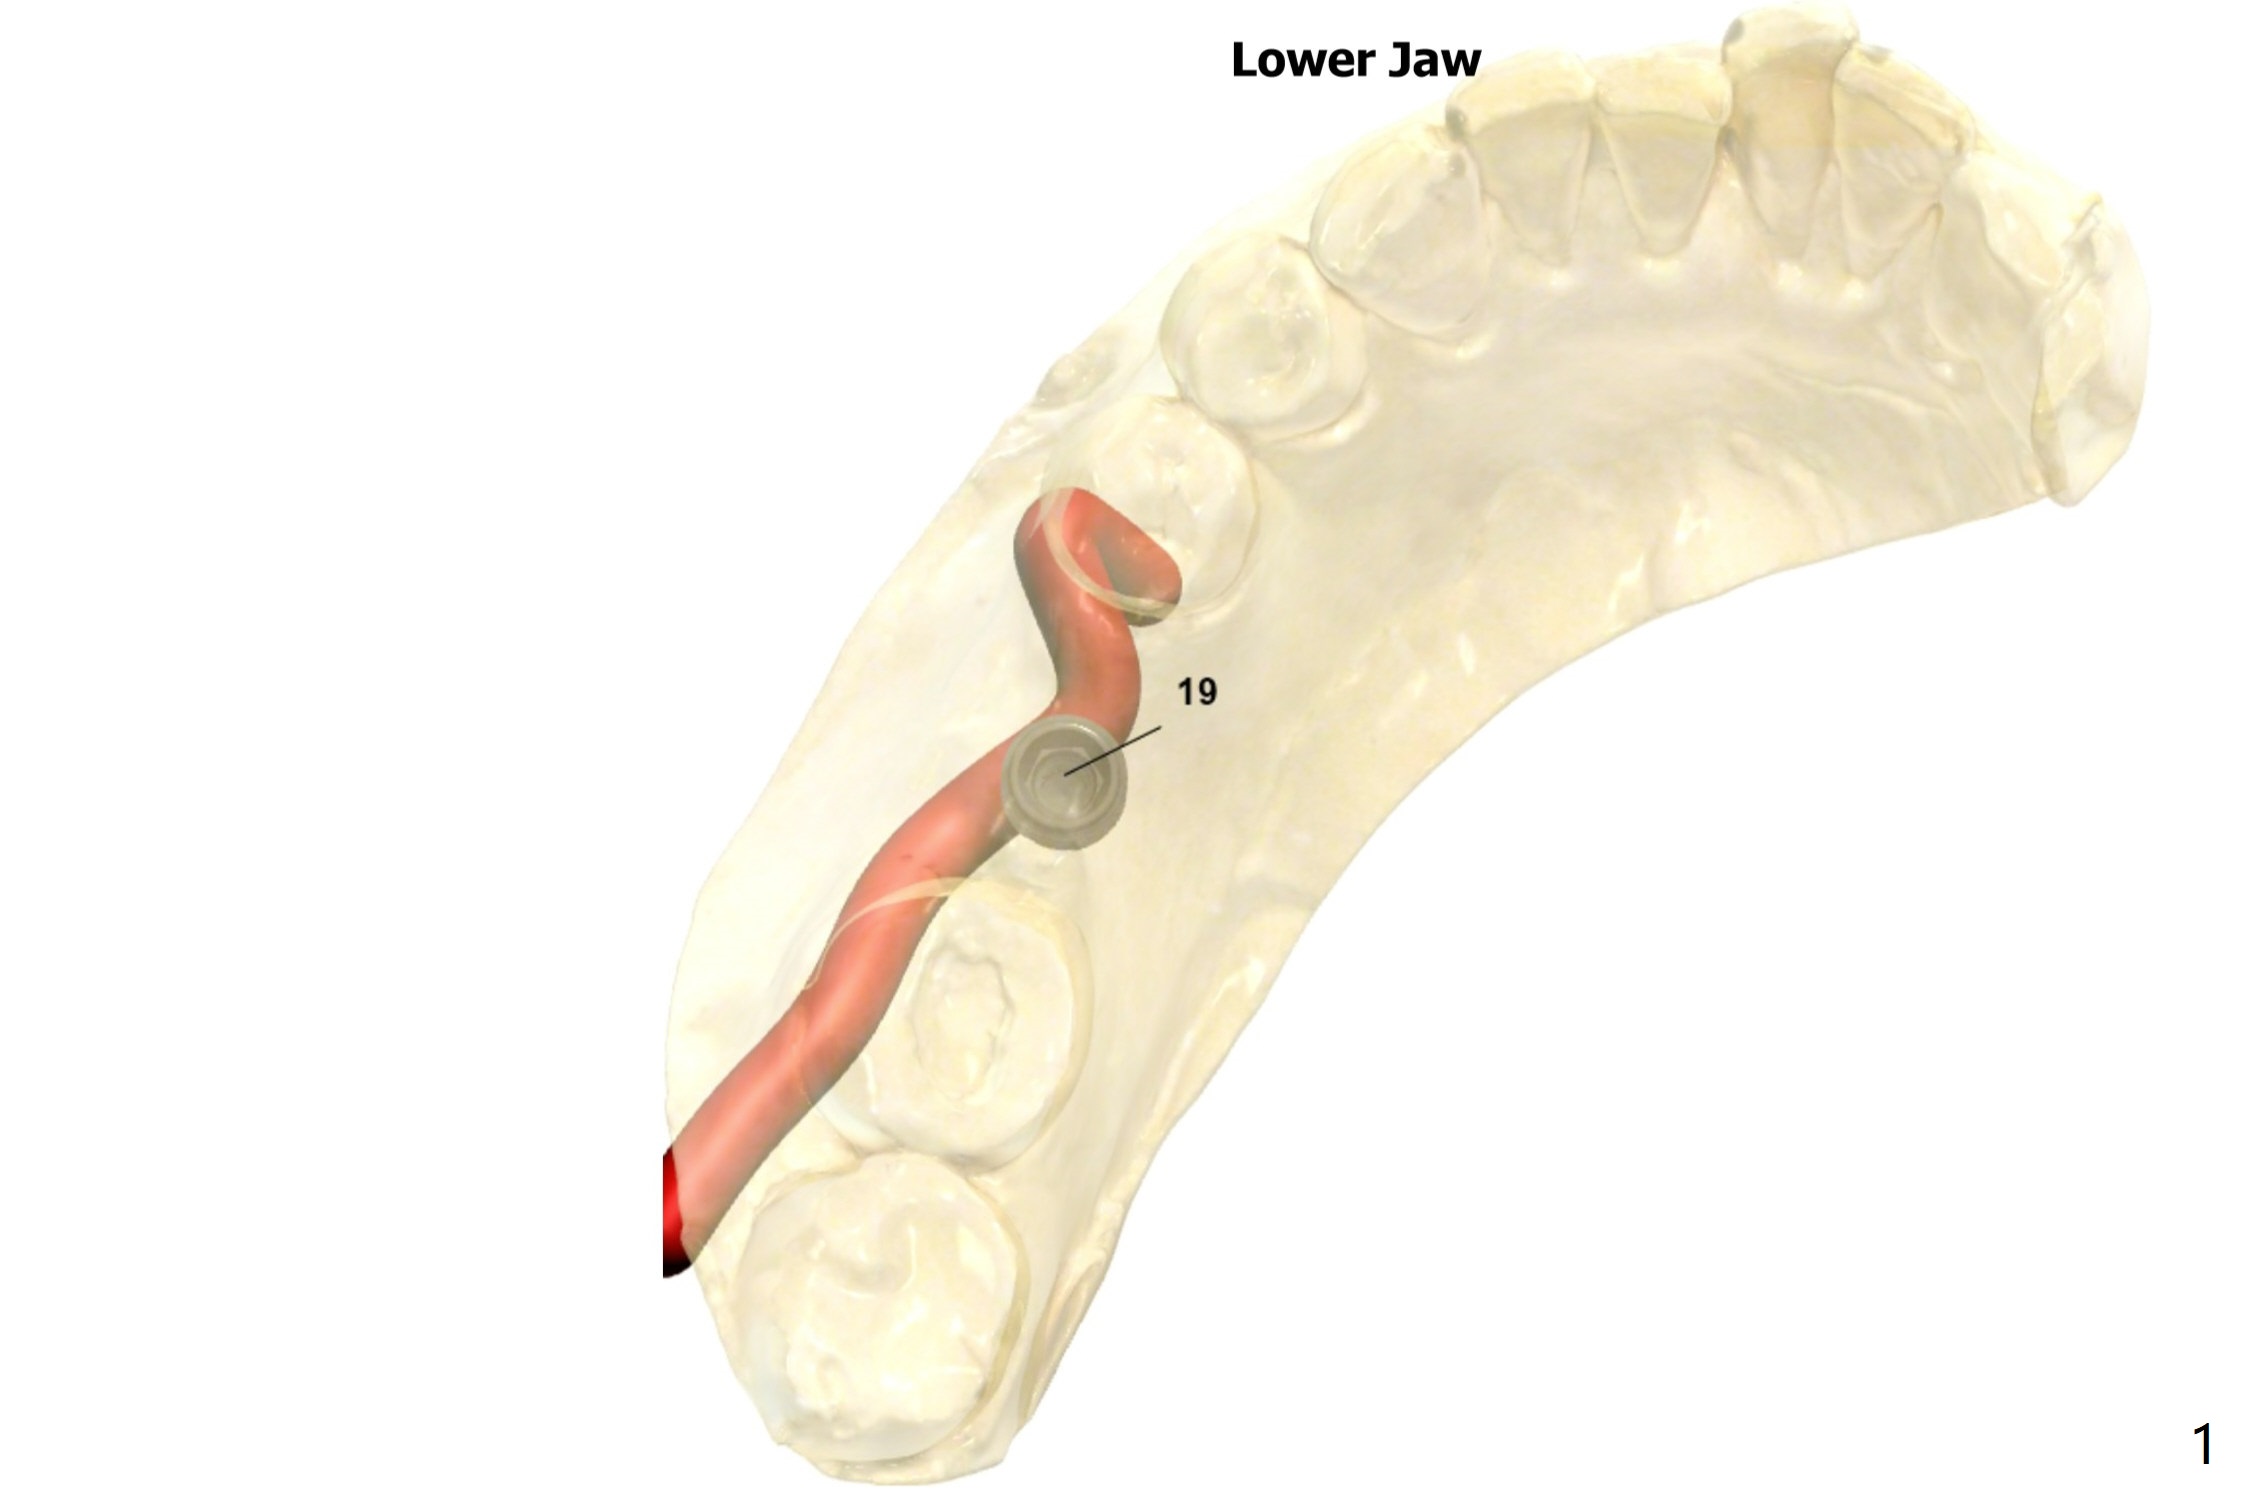

A narrow (extraction without bone graft) and short (accessory branch of nerve) implant is chosen at #19.